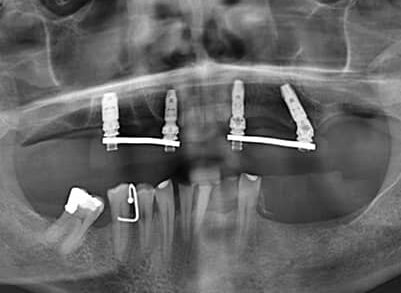

Treatment: Same Day Teeth & Cosmetic Dentures